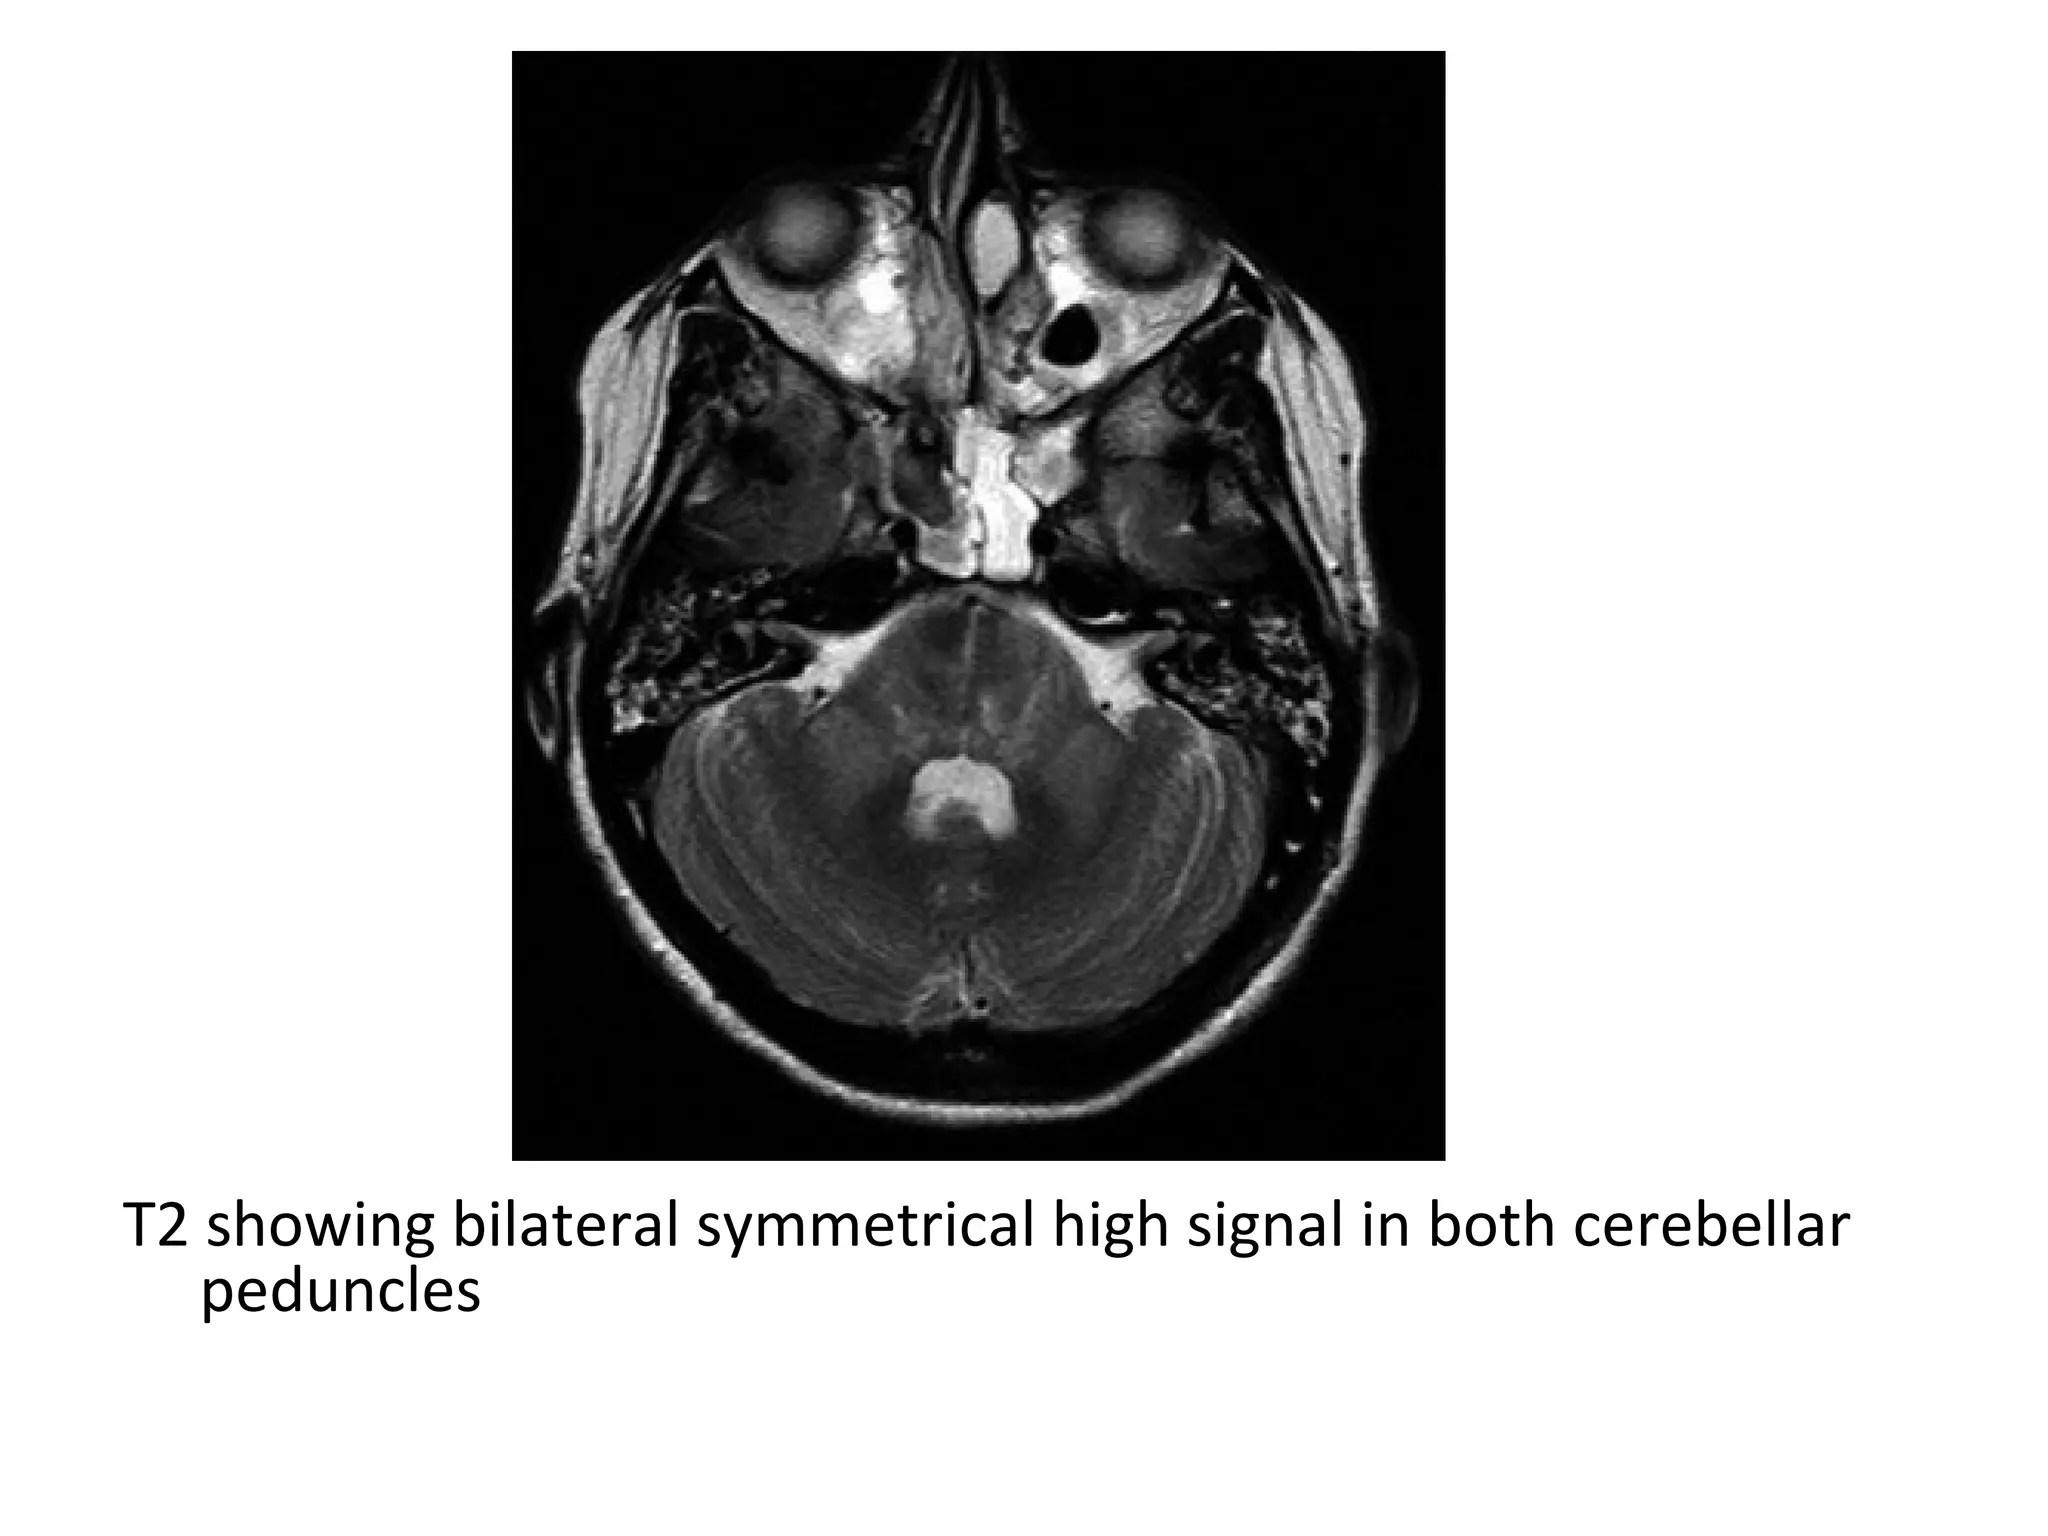

c) Radiographic Features :

-Hyperintensity on T2-weighted images along the affected tracts

-Conventional MRI depict WD when sufficiently large bundles of

fibers are involved along the corticospinal tract , the corpus

callosum , fibers of the optic radiations , fornices and

cerebellar peduncles

-The most common observations regard the corticospinal tract

-WD of cerebellar peduncles is rarely described , It usually

involves the middle ones because they are largest and the

main path for pontocerebellar tracts

T2 showing bilateral symmetrical high signal in both cerebellar

peduncles